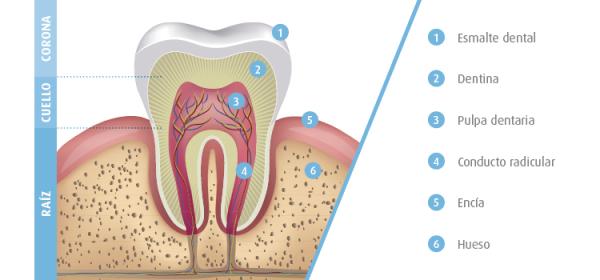

- Primera fase: es donde las caries empiezan a desarrollarse, en este punto el daño se produce en la parte más superficial y dura del diente, el esmalte, por esto es común que no se sienta dolor en este punto.

- Segunda fase: los dientes están compuestos de una sustancia llamada dentina y en esta fase esa área es la más afectada y comienza a aparecer el dolor.

- Tercera fase: a partir de aquí la caries avanza más rápidamente y alcanzará la pulpa dentaria, donde se encuentran los nervios y vasos sanguíneos del diente.

- Cuarta fase: es la más crítica, ya que la caries alcanzará los ligamentos periodontales, que unen el tejido al hueso, permitiendo que se formen abscesos e incluso provocar que el diente se desprenda.